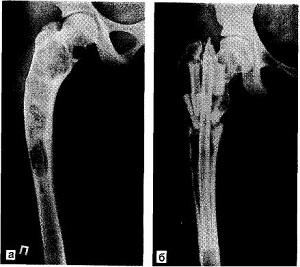

Бедренная кость

Фиброзная дисплазия бедренной кости приводит к интенсивным болям в области бедра и нарушает подвижность сустава, что затрудняет передвижение.

Хирургическое вмешательство в данном случае направлено на исправление поврежденной области с использованием подходящего по функциональным характеристикам трансплантата.

Терапия может считаться успешной только в том случае, если после завершения восстановительного периода не наблюдается рецидив.